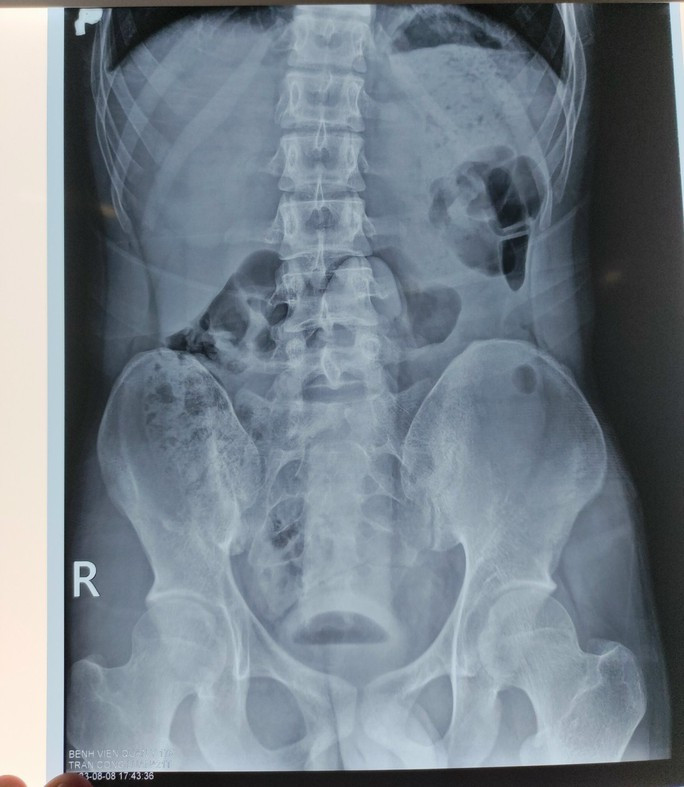

| Hình ảnh dị vật qua phim chụp Xquang |

Được biết với trường hợp bệnh nhân cấp cứu tại Bệnh viện Quân y 175, sau khi thăm khám và chụp Xquang, các bác sĩ phát hiện dị vật hình dạng giống dương vật nằm sâu trong trực tràng. Ngay sau đó nam thanh niên đã được chuyển lên Khoa Phẫu thuật - gây mê hồi sức để lấy dị vật ra.

Do kích thước dị vật lớn và lại nằm sâu trong trực tràng, rất dễ gây tổn thương cho bộ phận này, nên các bác sĩ lấy dị vật qua đường hậu môn một cách an toàn và không cần phẫu thuật.